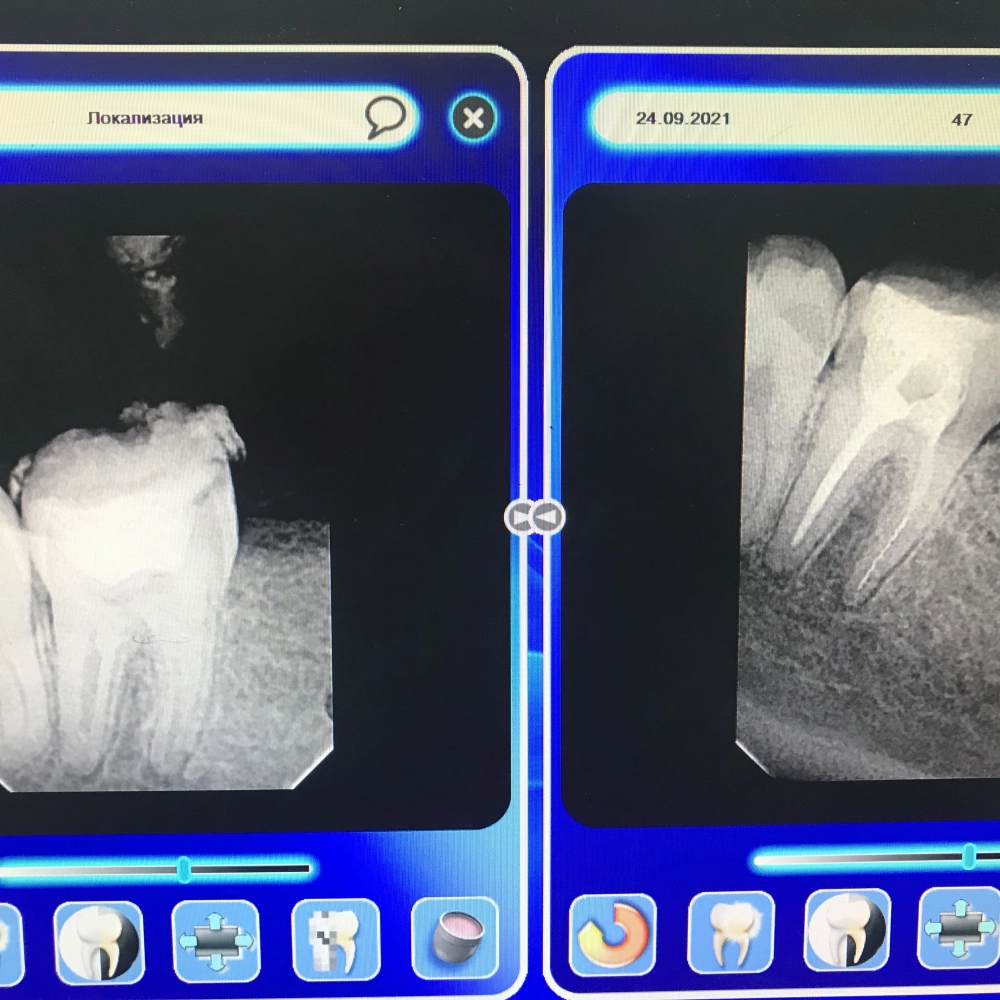

перелечивание зуба

До

После

перелечивание зубов